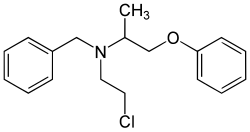

| Phenoxybenzamine | Dibenzyline |

Nonselective covalent binding to α1 and α2 receptors. | Lowers blood pressure by decreasing peripheral resistance.

Blocks alpha induced vasconstriction.[2] |

Phenoxybenzamine, a nonselective α1 and α2 blocker, has been used to treat pheochromocytoma.[21] This drug blocks the activity of epinephrine and norepinephrine by antagonizing the alpha receptors, thus decreasing vascular resistance, increasing vasodilation, and decreasing blood pressure overall.[21]

Phenoxybenzamine, a non-competitive α1 and α2 blocker was used by Dr. Giles Brindley in the first intracavernosal pharmacotherapy for erectile dysfunction.[24]

As with any drug, there are drug interactions that can occur with alpha blockers. For instance, alpha blockers that are used for the reduction of blood pressure, such as phenoxybenzamine or phentolamine can have synergy with other drugs that affect smooth muscle, blood vessels, or drugs used for erectile dysfunction (i.e. sildenafil, tamsulosin, etc.). This stimulates exaggerated hypotension.[2]